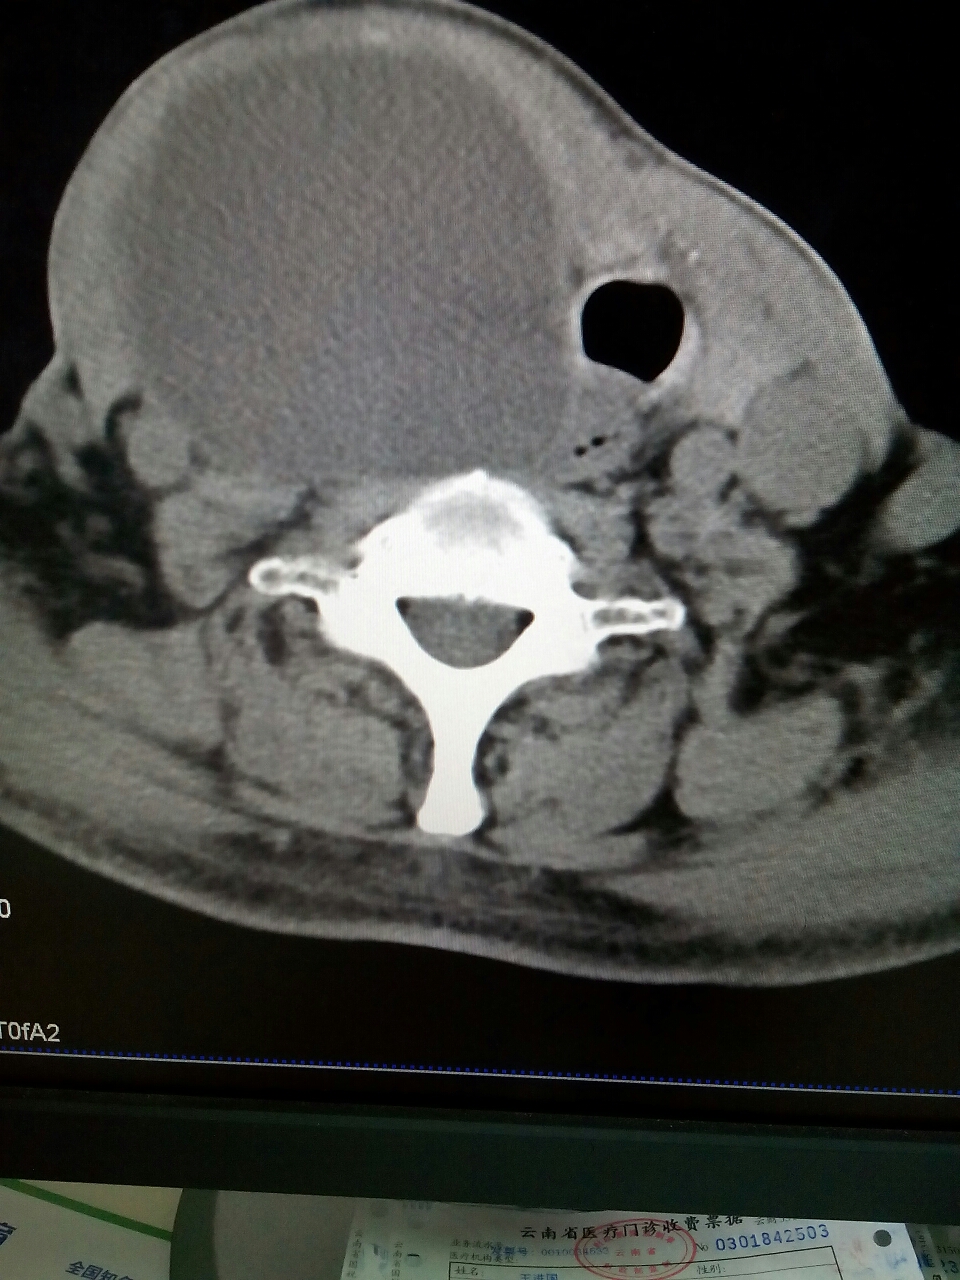

CT51633:甲状腺区

本帖最后由 cefcmj 于 2016-3-7 18:23 编辑 甲状腺囊肿?

是甲状腺囊性肿物的印象,内容物猜不好。

支持甲状腺囊肿

右侧甲状腺囊肿。

右侧甲状腺囊肿?